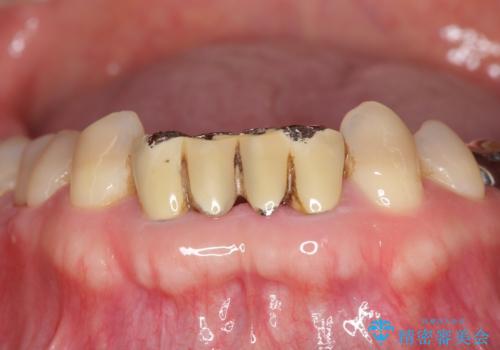

かみ合わせが強く、以前入っていた保険治療のブリッジも前装が欠けてしまっていました。

セラミックも強い衝撃で欠けないわけではないため、強度のあるフルジルコニアクラウンでブリッジを作成しました。